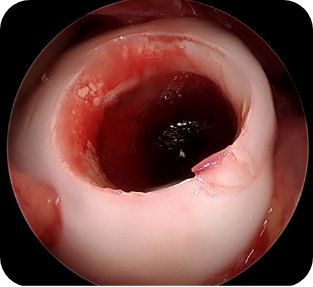

• ▲ 자가 골연골 이식술 전

• ▲ 자가 골연골 이식술 중

• ▲ 자가 골연골 이식술 후

• 5) 관절경하 자가 골연골 이식술

국소부위 연골에 손상이 있는 관절염이나 연골 혈액순환의 장애가 생겨 떨어지는 박리성 골연골염 등의 환자에서 시행하는 수술 방법으로, 환자의 관절 내에 체중부하를 받지 않는 골관절 연골을 채취하여 손상부위에 이식해 주는 치료 방법입니다.

수술방법

관절경 탐색 후 손상되어 있는 연골 부분을 뼈를 포함한 원통형 모양으로 제거 후, 환자 관절 내에 체중을 받지 않는 부위의 건강한 연골부위를 같은 모양으로 채취하여 제거된 연골부위에 옮겨주는 수술입니다.

수술장점

한 번의 수술로 결손부위를 건강한 연골로 채워줄 수 있으며, 본인의 연골을 옮겨주는 방법이기 때문에 거부반응이 없습니다. 절개 부위도 크지 않아 상처 회복에 문제가 생길 가능성이 적습니다.